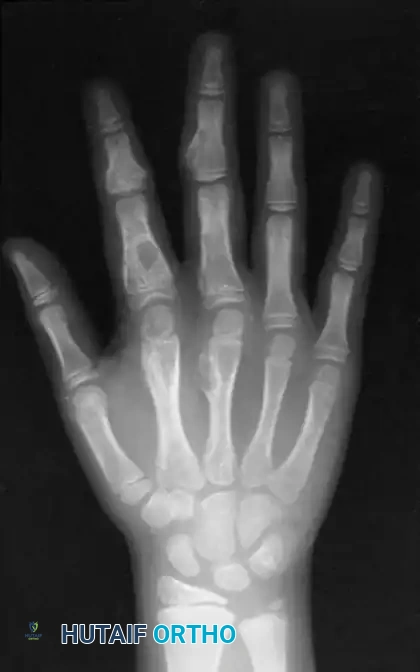

Radiographically, ABCs are almost indistinguishable from giant cell tumors or highly expansile enchondromas. They present as radiolucent, multiloculated ("soap bubble") lesions that cause tremendous cortical expansion, often reducing the cortex to a microscopic, eggshell-thin rim.

Radiographic presentation of an eccentric, ballooning lytic lesion characteristic of an aneurysmal bone cyst or aggressive osteoid osteoma variant in the proximal phalanx.